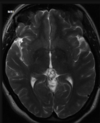

Q

A

Esclerose mesial temporal

Observe a perda de volume, que indica atrofia e causa aumento secundário do corno temporal do ventrículo lateral.

O sinal alto no hipocampo reflete a gliose.

How well did you know this?

Qual o padrão da Esclerose mesial temporal?

Atrofia hipocampal e hipersinal T2. Cerca de 10% dos casos são bilaterais (dificulta o diagnóstico). A etiologia é desconhecida, mas há uma relação entre STM e convulsões febris prolongadas no início da vida A esclerose mesial temporal pode ocorrer em associação com outras patologias, principalmente displasia cortical focal (dual pathology).